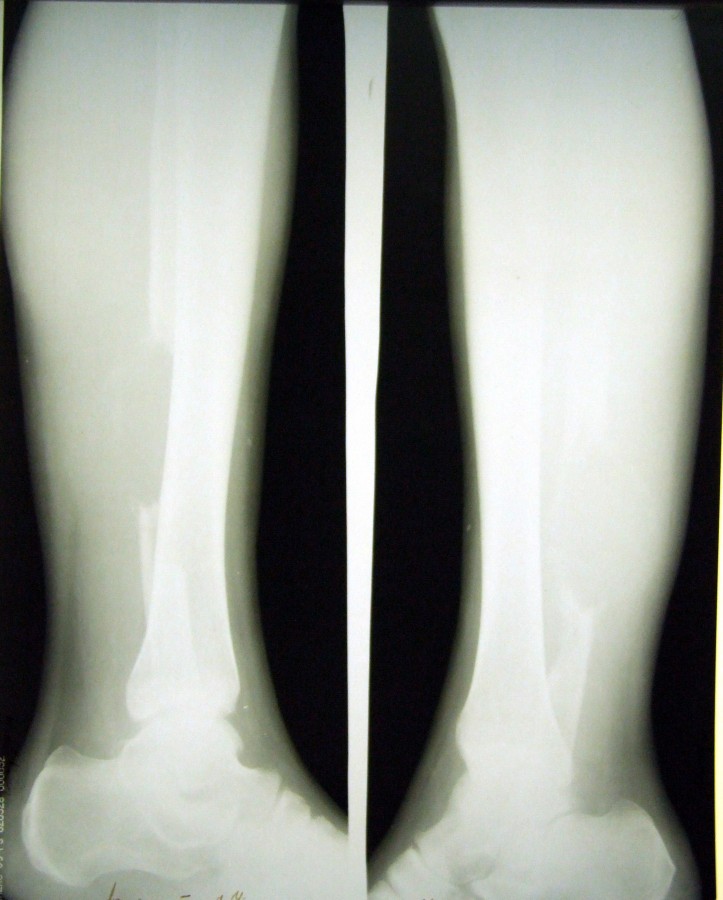

Заголовок сообщения: Саркома, ноги

Обсуждалась здесь download/file.php?id=20349&t=1